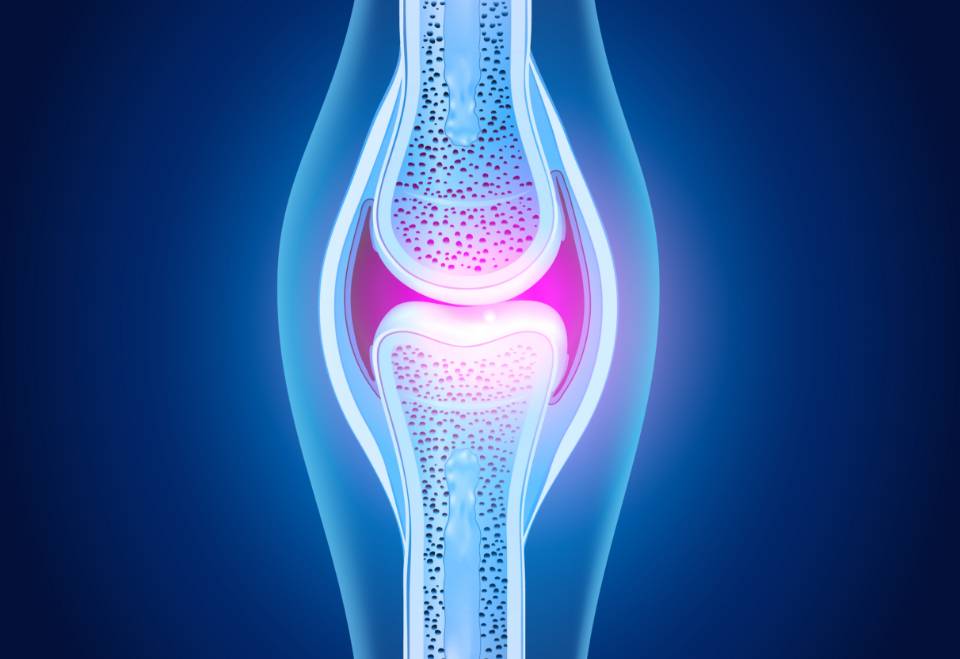

ATUAÇÃO DO NUTRIENTE CONDROITINA

Para quem é indicada a Condroitina?

A suplementação de condroitina é indicada para atletas, adeptos e não adeptos (sedentários) aos exercícios físicos e pessoas que receberam indicação médica para tratamentos como osteoporose.